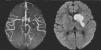

Niña de 7 años que acude a urgencias con hemiparesia derecha de inicio súbito con 30min de evolución. El hemograma inicial, así como la velocidad de sedimentación, bioquímica y proteína C reactiva resultaron normales. La tomografía computarizada craneal fue normal, por lo que se realizó resonancia magnética con angioresonancia (ARM) (fig. 1). Se instauró tratamiento de soporte general y se realizaron estudios complementarios: panel completo de autoanticuerpos, serología para familia Herpesviridae, ecografía Doppler de vasos cervicales y ecocardiograma transtorácico, sin encontrarse alguna anormalidad que explicara el ictus.

Estudio vascular por angioresonancia magnética realizado durante la etapa aguda del padecimiento, muestra un defecto de llenado irregular en el calibre y forma del segmento M1 izquierdo sin compromiso de la circulación distal. A la derecha, secuencia de difusión por resonancia magnética, muestra imagen hiperintensa localizada en la cabeza del núcleo caudado, capsula interna y núcleo lenticular consistente con infarto agudo.